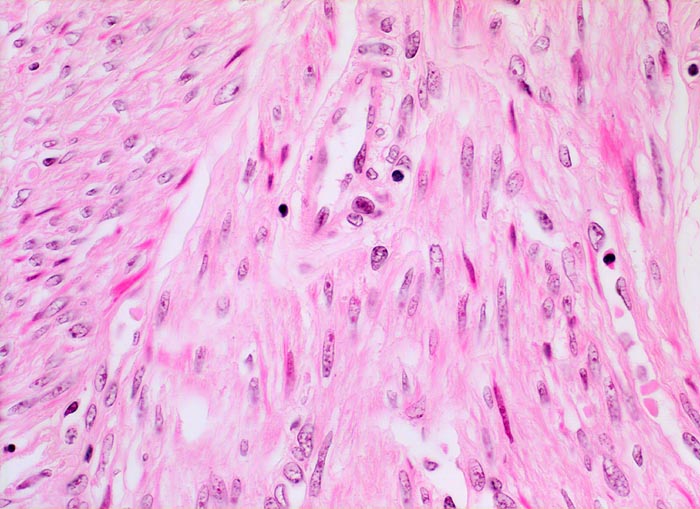

PathoPic – image database / PathoPic ID 4440 - Fibroleiomyom des Uterus

Fibroleiomyom des Uterus

Die glattmuskulären Tumorzellen bilden geflechtartig verwobene Bündel. Zwischen den Tumorzellen verlaufen unterschiedlich breite zellarme Kollagenfaserzüge und dünnwandige Gefässe. Vereinzelte Entzündungszellen.

Vergrösserter 258g schwerer Uterus mit multiplen weissen, derben scharf begrenzten, teils intramuralen und teils submukös gelegenen Knoten.